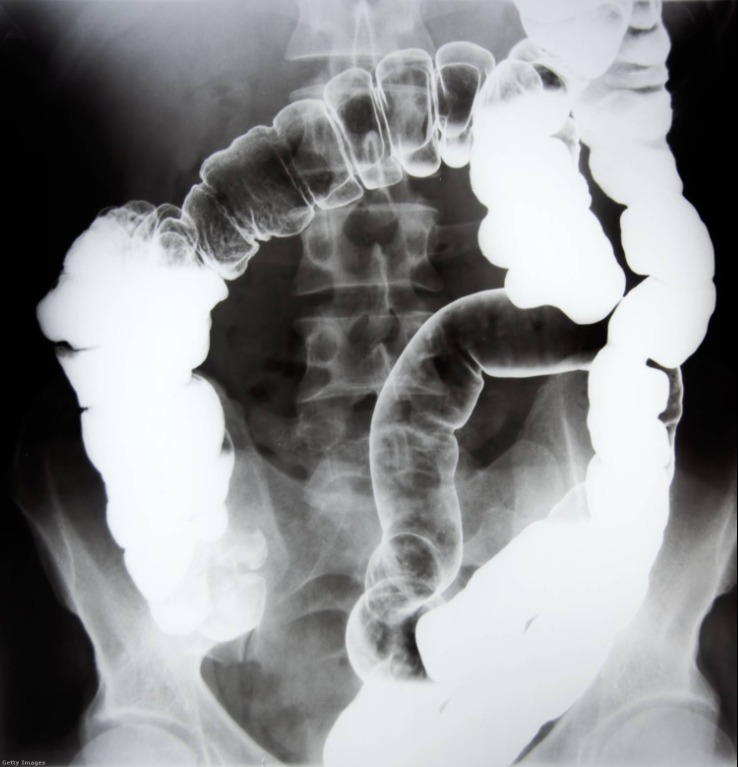

A vizsgálatok során az orvosok olyan képet láttak a röntgenen, amire senki sem számított: a férfi nyelőcsövében egy óra, a vastagbelében pedig vasdarabok, anyák és csavarok voltak.

Sokkoló, mit találtak a férfi hasábanA sebészek azonnal megkezdték a háromórás műtétet, hogy eltávolítsák a tárgyakat. A beavatkozás során egy apró hasi bemetszésen keresztül sikerült mindent kiszedni, és a műtőben készült felvételek szerint az orvosok maguk is megdöbbentek azon, mennyi idegen tárgy volt a beteg testében. A férfit október 9-én vették fel, és a műtét után szerencsére javulni kezdett az állapota.